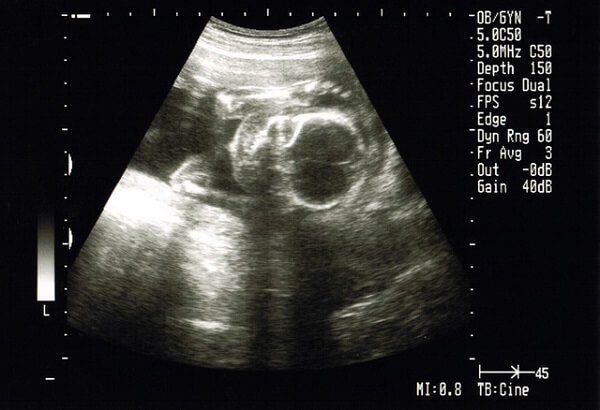

妊娠6ヶ月(20~23週)メロン中玉1個くらいの重さ

身長約30㎝、体重約700gです。超音波検査画面に全身が一度にはうつりきらないほど大きくなってきます。初産婦さんもこの頃からはっきりと胎動を感じはじめます。

発育スピードは前月より遅くなりますが、その分臓器が成熟してきます。このころには、生殖器も発達してきて、エコーでも性別がはっきりみてとれるようになります。